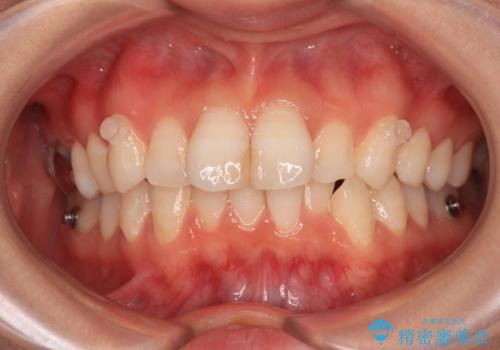

- 上下前歯のデコボコを改善したいとのことで来院された患者様です。

マウスピースを長時間装着し続ける自信はあまりないとのことでしたが、目立たない装置であれば頑張って装着するとのことで、インビザラインによる矯正治療を行うこととしました。

初めの1年くらいは何とか頑張って装着してくださいましたが、途中から変化をあまり感じられなくなり、日々の装着時間は徐々に短くなってしまいました。

前歯のデコボコはもっと改善できましたが、3年半が経過し、初診時と比べたら大幅に良くなったとのことで終了することとなりました。